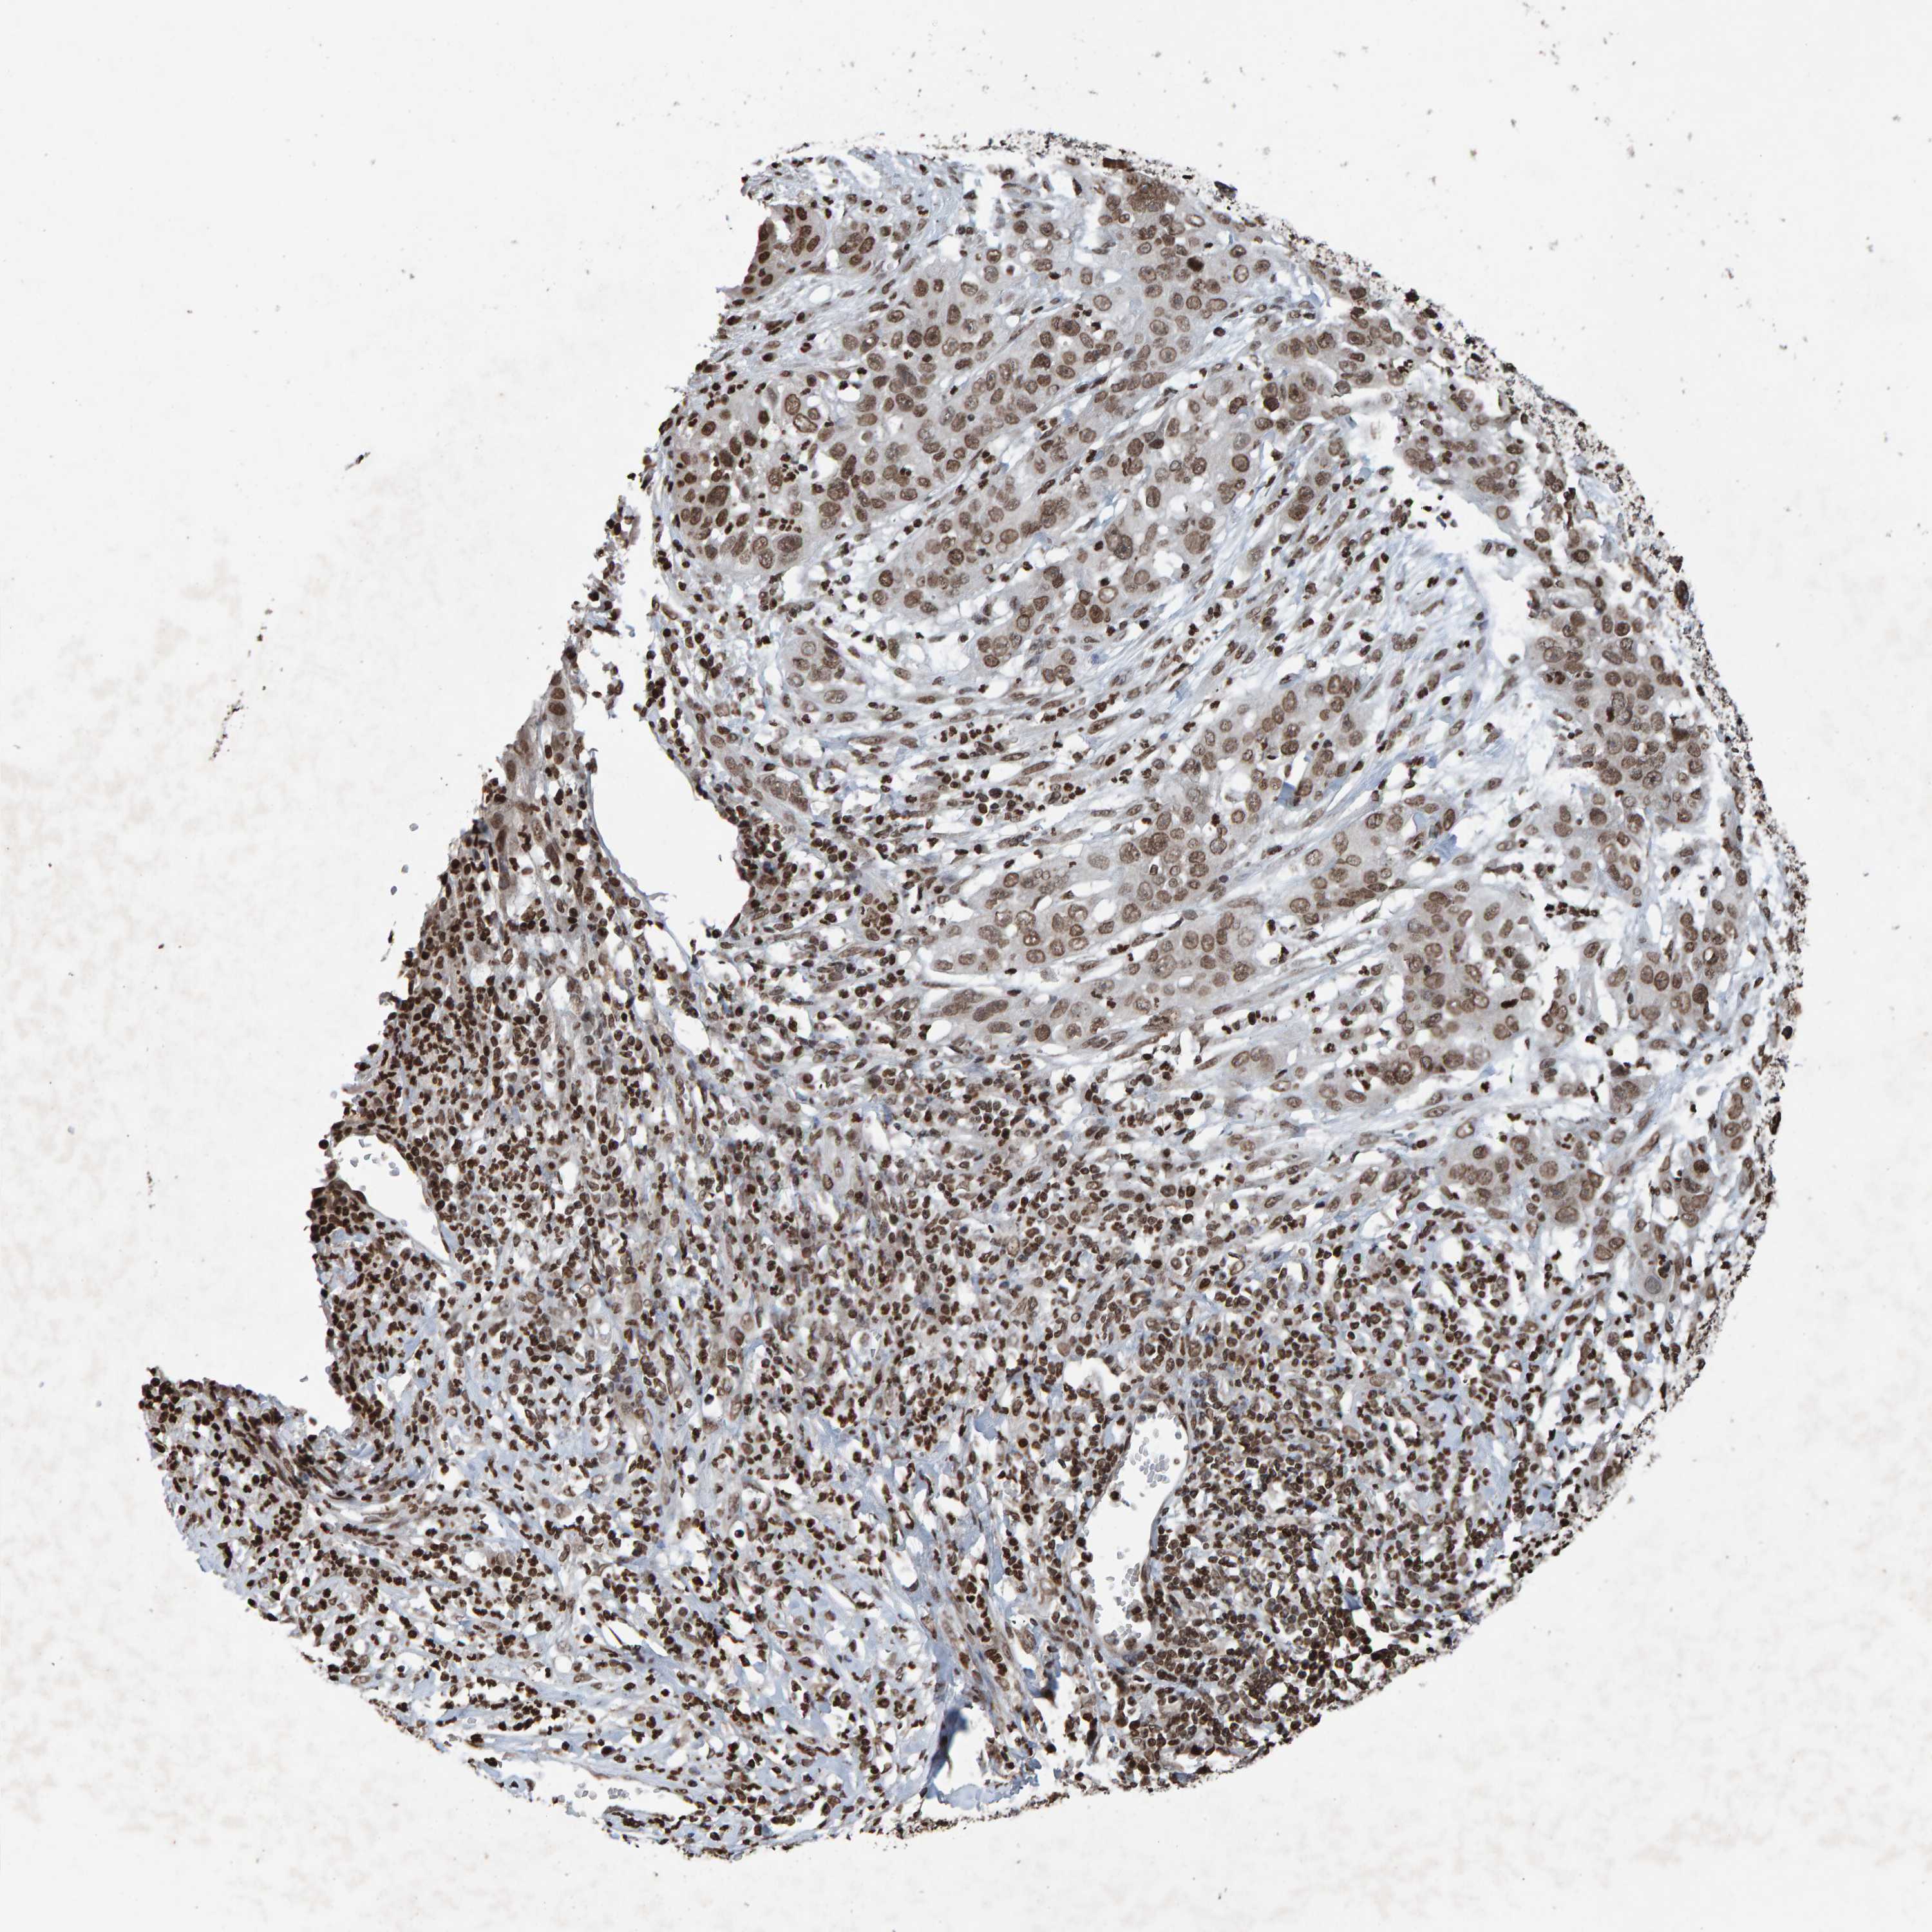

CERVICAL CANCER - Protein expressioni

A mouse-over function shows sample information and annotation data. Click on an image to view it in a full screen mode. Samples can be filtered based on level of antibody staining by selecting one or several of the following categories: high, medium, low and not detected. The assay and annotation is described here.

Note that samples used for immunohistochemistry by the Human Protein Atlas do not correspond to samples in the TCGA dataset.

Antibody stainingi

Antibody staining in the annotated cell types in the current human tissue is reported as not detected, low, medium, or high, based on conventional immunohistochemistry profiling in selected tissues. This score is based on the combination of the staining intensity and fraction of stained cells.

Each image is clickable and will lead to virtual microscopy that enables deeper exploration of all samples and also displays staining intensity scores, fraction scores and subcellular localization as well as patient and tissue information for each sample.

Antibody HPA057236

Antibody CAB022549

Staining

High

Medium

Low

Not detected

Intensity

Strong

Moderate

Weak

Negative

Quantity

>75%

75%-25%

<25%

None

Location

Nuclear

Cytoplasmic/membranous

Cytoplasmic/membranous,nuclear

Squamous cell carcinoma, NOS

Adenocarcinoma, NOS